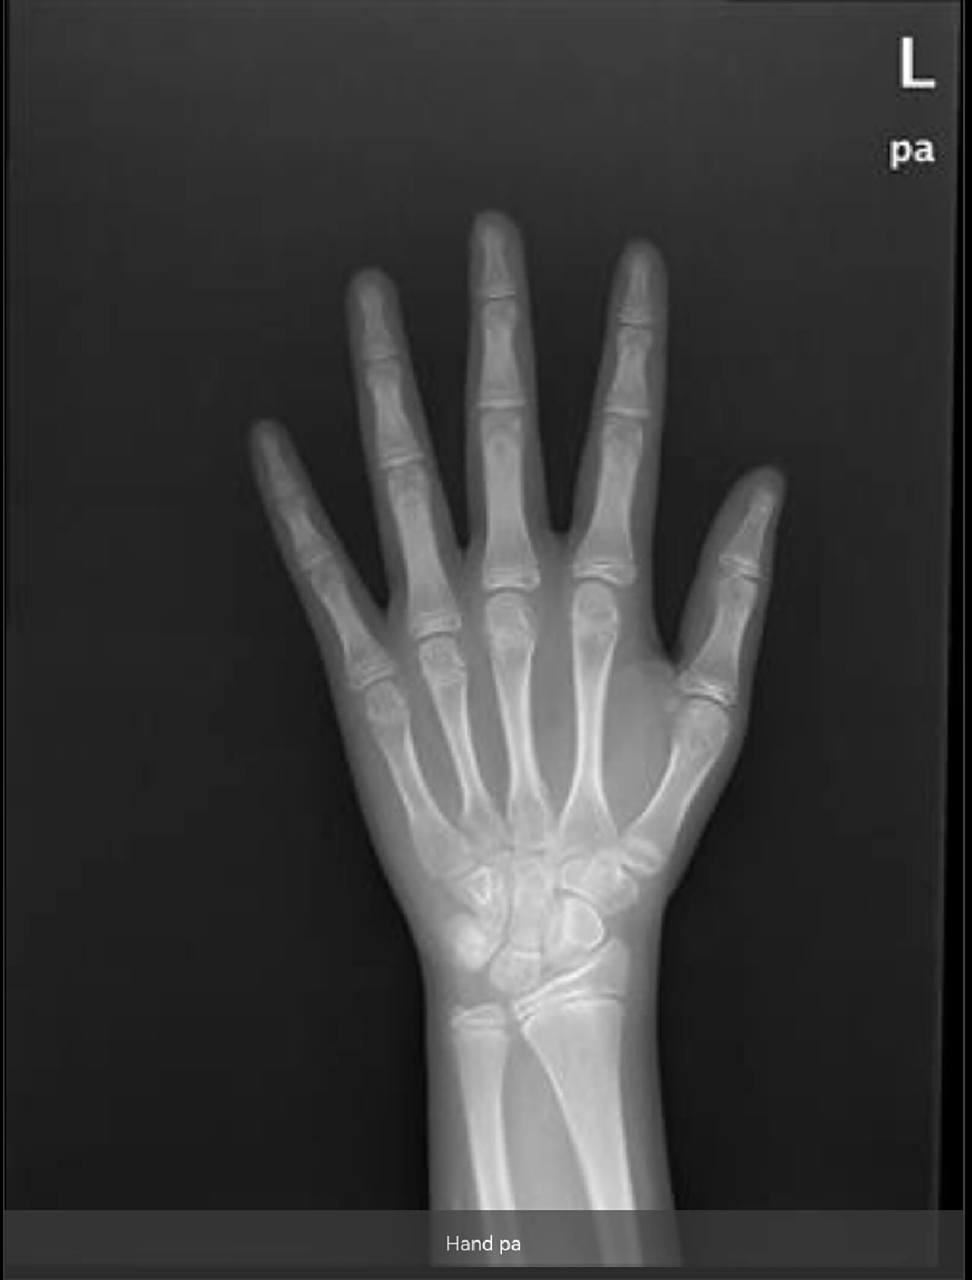

"左胳膊肘:左桡骨小头后侧不连缘,肱骨小头后缘部分缺损,疑是骨折"

图片尺寸1080x607